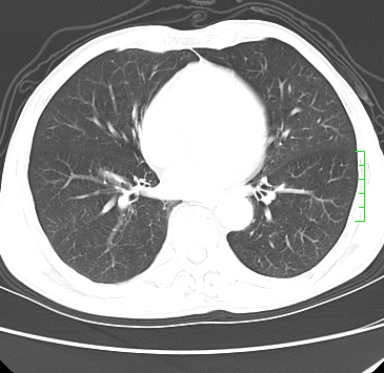

m,73y。膝关节疼痛伴双下肢水肿。入院常规胸片发现结节灶。增强为静脉期。

浅分叶、棘突,考虑右下肺周围型肺癌

考虑周围型肺癌  ,双上肺结核。

肿块周围可见局限性气肿,考虑肺癌可能性大。双肺上叶继发型肺结核。

指套征,强化明显,近侧肺组织局限性肺气肿,考虑支气管类癌,慢支、肺气肿、双上陈旧性tb、冠脉钙化。

鉴别:先天性支气管闭锁,变态反应性支气管肺曲霉菌病,肺癌,支气管囊肿,支扩黏液嵌塞。

1)考虑右肺下叶周围型肺癌。2)右肺上叶及左肺感染性病变(结核可能)。3)肺气肿。4)冠状动脉钙化。